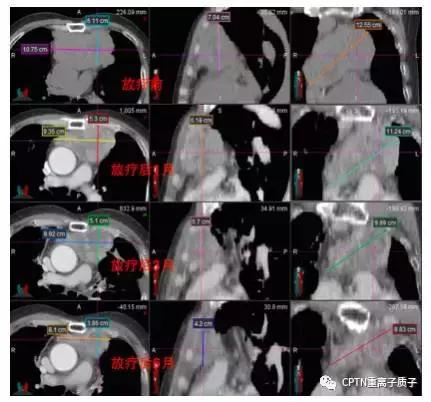

不典型类癌患者,因高龄(74岁)、肿瘤巨大(11*8cm),手术风险大而拒绝手术治疗,且这类肿瘤通常对常规光子放疗和化疗均不敏感。患者接受根治性质子重离子放疗。肿瘤在放疗结束后1-9个月间持续缩小,放疗结束后15月最后一次复查时仍维持肿瘤受控状态。治疗不良反应包括轻度恶心、放射性肺炎和窦性心动过速等,放疗后3月内均明显缓解。